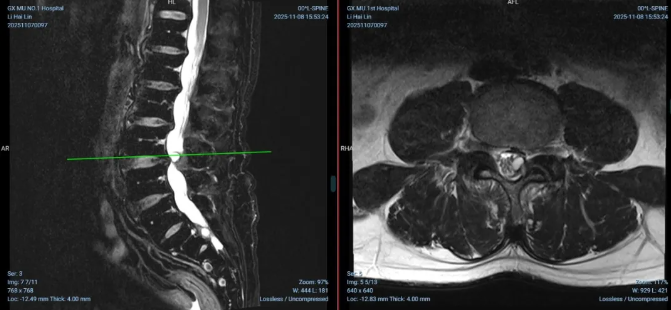

▲术前 MRI 显示右侧侧隐窝狭窄及腰椎右侧囊肿

入院后,我院脊柱骨病外科刘云教授团队深入研判,结合影像学与临床体征,明确其核心致病因素为「右侧侧隐窝狭窄」。这一病变与患者表现为右下肢痛麻的神经根性症状高度契合,是导致其痛苦的主要原因。影像学同时还发现了一处位于左侧的腰椎囊肿,虽未引起明显症状,但囊肿体积较大,但毗邻硬膜边界,特征不典型,难以明确区分其位于硬膜外还是硬膜下,存在远期增大并压迫神经的风险,具备明确的手术指征。

根据术前影像检查显示,一处是引发当前症状的「元凶」(右侧侧隐窝狭窄),另一处是潜伏的「定时炸弹」(腰椎囊肿)的复杂情况,这一「两病齐发」的情况,为手术方案的制定带来巨大挑战:若误判囊肿性质,可能导致手术范围不足或神经损伤风险增加,传统手术方式可能造成创伤大、恢复慢等不足。面对这一难题,刘云团队经过周密评估,果断选择 AUSS 微创技术,希望通过一次手术、一个微创切口,同时精准解决两处病变,术中实时直视下精准探查与病变彻底清除,让患者免受二次手术之苦。